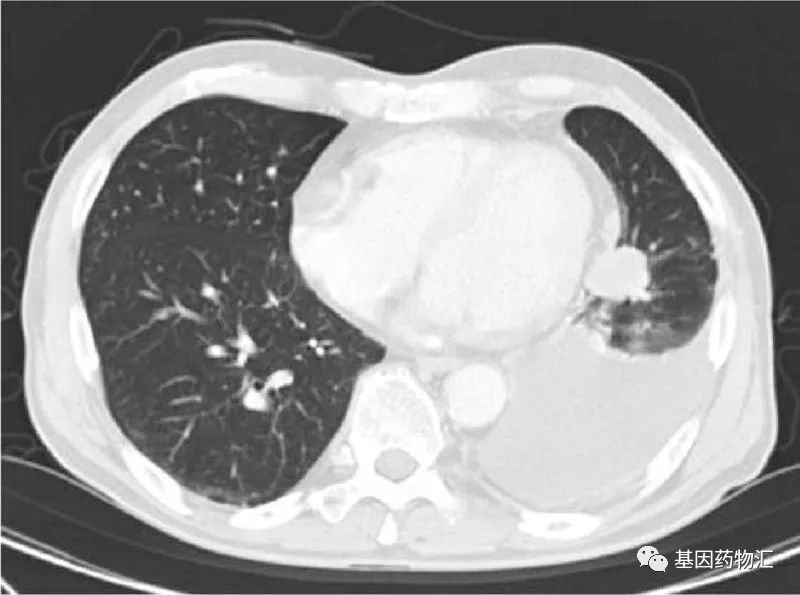

这位患者为71岁男性,于2007年8月确诊了Ⅳ期肺癌(T4N0M1a)。左下肺叶有一个3厘米直径的肿瘤病灶,左上叶有一个5毫米直径的结节,被认为是转移病灶。

图片来源:《奥希替尼在非小细胞肺癌靶向治疗中的获得性耐药机制》DOI: 10.3779/j.issn.1009-3419.2020.103.0